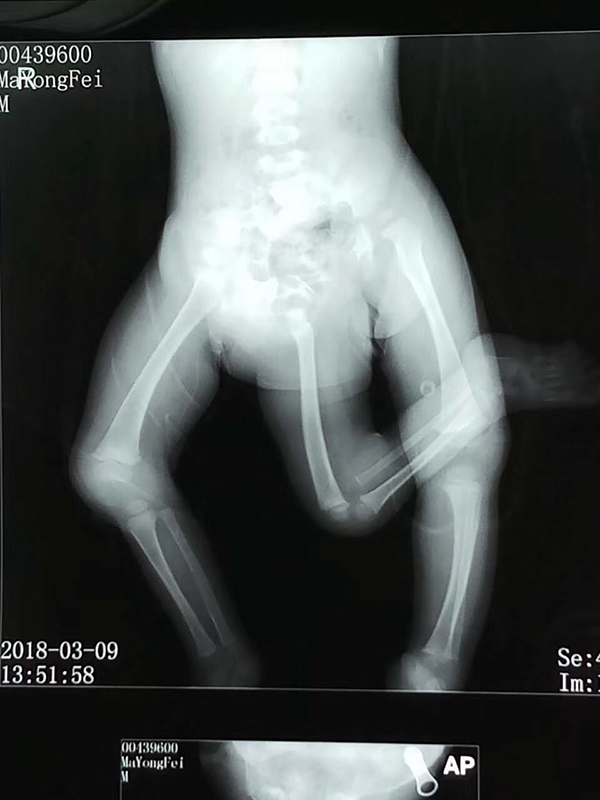

影像學檢查。嚴曉慧供圖

影像學檢查。 嚴曉慧供圖